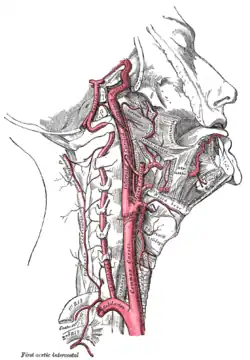

In the neck

Each vessel passes obliquely upward, from behind the sternoclavicular joint to the level of the upper border of the thyroid cartilage, where it divides.

At the lower neck, the two common carotid arteries are separated from each other by a very narrow interval which contains the trachea; but at the upper part, the thyroid gland, the larynx and pharynx separate the two arteries.

The common carotid artery is contained in a sheath known as the carotid sheath, which is derived from the deep cervical fascia and encloses also the internal jugular vein and vagus nerve, the vein lying lateral to the artery, and the nerve between the artery and vein, on a plane posterior to both. On opening the sheath, each of these three structures is seen to have a separate fibrous cover.

At approximately the level of the fourth cervical vertebra, the common carotid artery splits ("bifurcates" in literature) into an internal carotid artery (ICA) and an external carotid artery (ECA). While both branches travel upward, the internal carotid takes a deeper (more internal) path, eventually travelling up into the skull to supply the brain. The external carotid artery travels more closely to the surface, and sends off numerous branches that supply the neck and face.

At the lower part of the neck, the common carotid artery is very deeply seated, being covered by the integument, superficial fascia, the platysma muscle, deep cervical fascia, the sternocleidomastoid muscle, the sternohyoid, sternothyroid, and the omohyoid; in the upper part of its course it is more superficial, being covered merely by the integument, the superficial fascia, the platysma, deep cervical fascia, and medial margin of the sternocleidomastoid.

When the sternocleidomastoid muscle is drawn backward, the artery is seen to be contained in a triangular space known as the carotid triangle. This space is bounded behind by the sternocleidomastoid, above by the stylohyoid and the posterior belly of the digastric muscle, and below by the superior belly of the omohyoid.

This part of the artery is crossed obliquely, from its medial to its lateral side, by the sternocleidomastoid branch of the superior thyroid artery; it is also crossed by the superior and middle thyroid veins (which end in the internal jugular vein); descending in front of its sheath is the descending branch of the hypoglossal nerve, this filament being joined by one or two branches from the cervical nerves, which cross the vessel obliquely.

The superior thyroid vein crosses the artery near its termination, and the middle thyroid vein a little below the level of the cricoid cartilage; the anterior jugular vein crosses the artery just above the clavicle, but is separated from it by the sternohyoid and sternothyroid.

Behind, the artery is separated from the transverse processes of the cervical vertebrae by the longus colli and longus capitis muscles, the sympathetic trunk being interposed between it and the muscles. The inferior thyroid artery crosses behind the lower part of the vessel.

Medially, it is in relation with the esophagus, trachea, and thyroid gland (which overlaps it), the inferior thyroid artery and recurrent laryngeal nerve being interposed; higher up, with the larynx and pharynx. Lateral to the artery, inside the carotid sheath with the common carotid, are the internal jugular vein and vagus nerve.

At the lower part of the neck, on the right side of the body, the right recurrent laryngeal nerve crosses obliquely behind the artery; the right internal jugular vein diverges from the artery. On the left side, however, the left internal jugular vein approaches and often overlaps the lower part of the artery.